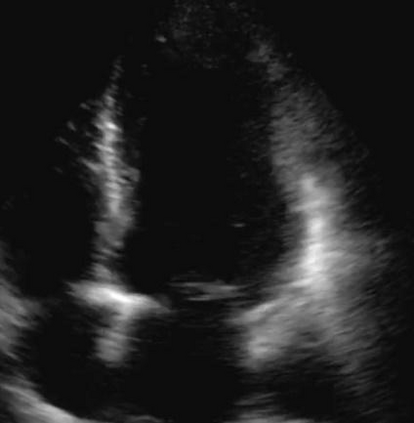

Most deep neural networks (DNNs) based ultrasound (US) medical image analysis models use pretrained backbones (e.g., ImageNet) for better model generalization. However, the domain gap between natural and medical images causes an inevitable performance bottleneck. To alleviate this problem, an US dataset named US-4 is constructed for direct pretraining on the same domain. It contains over 23,000 images from four US video sub-datasets. To learn robust features from US-4, we propose an US semi-supervised contrastive learning method, named USCL, for pretraining. In order to avoid high similarities between negative pairs as well as mine abundant visual features from limited US videos, USCL adopts a sample pair generation method to enrich the feature involved in a single step of contrastive optimization. Extensive experiments on several downstream tasks show the superiority of USCL pretraining against ImageNet pretraining and other state-of-the-art (SOTA) pretraining approaches. In particular, USCL pretrained backbone achieves fine-tuning accuracy of over 94% on POCUS dataset, which is 10% higher than 84% of the ImageNet pretrained model. The source codes of this work are available at https://github.com/983632847/USCL.

翻译:大部分深心神经网络(DNNS)基于超声波(美国)的超声波医学图像分析模型使用预先训练的脊椎(如图像网络)来进行更好的模型化分析。然而,自然图像和医疗图像之间的领域差距造成了不可避免的性能瓶颈。为了缓解这一问题,为在同一领域直接训练建造了一个名为US-4的美国数据集。该数据集包含来自四个美国视频子数据集的23 000多张图像。为了从美国-4中学习强健的特征,我们提议了美国半监督的对比学习方法,名为USCL(USCL),用于预培训。为了避免负面对子与有限的美国视频中丰富的地雷视觉特征之间的高度相似性,USCL采用了一种样品配对生成方法来丰富单步对比性优化所涉及的特征。关于一些下游任务的广泛实验显示了USCL对图像网络预培训和其他状态艺术预培训方法的优势。特别是,USCLU预先训练的骨架在POCS数据集上实现了94 %的微调精准性精确度,这在图像网络上比84%高10 %/MUSPASTASTASTRAIN premstrain practresmex pract press press rodustrismex sramduction sramduction sramduction sramduction surgles)。